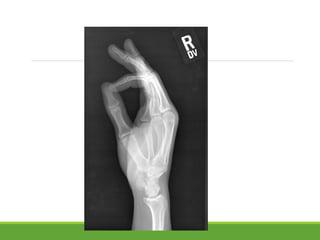

• #41 How many fingers was he raising ?